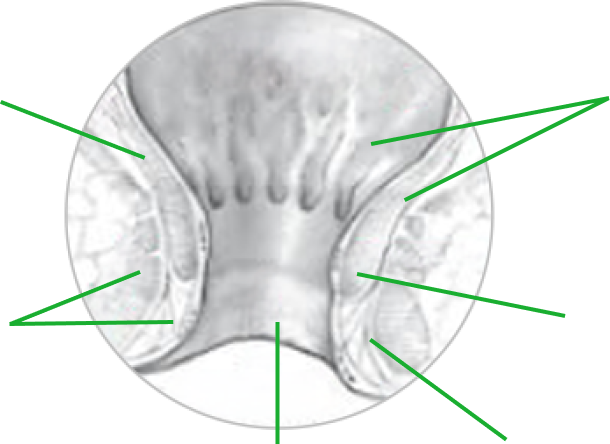

Zdrowy odbyt

ZDROWA ODBYTNICA

Ścianka mieśniowa

Mięsień zwieracza zewnętrznego

Błona śluzowa

Mięsień zwieracza wewnętrznego

Kanał odbytu

Skóra